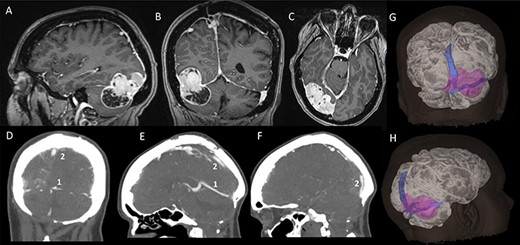

A 48-year-old, right-hand-dominant lady was under surveillance for a known right tentorial meningioma. At the age of 19, she had a posterior fossa craniectomy and resection of medulloblastoma, which was followed by cranio-spinal radiotherapy. She developed intracranial meningiomas presumably as a consequence of radiation exposure. The tentorial meningioma had progressed radiologically on surveillance imaging over 5 years. It had grown around the right transverse sinus and involved the torcula, sagittal sinus and, to some extent, the straight sinus. Cerebral CT venography showed the meningioma was causing stenosis of the posterior third of the superior sagittal sinus (Sindou Type III sinus invasion) and the right transverse sinus was almost completely occluded (Type IV). Filling defects were seen in the torcula, however, the left transverse sinus and straight sinus were predominantly patent (Fig. 1). After discussion of her case at our neuro-oncology multi-disciplinary meeting, we offered her surgical resection of the meningioma.

Pre-operative imaging; (A–C) sagittal, coronal and axial T1-weighted MRI images, with gadolinium demonstrating a supra-infratentorial peritorcular tumour; (D–F) CT venogram showing the patency of the straight sinus (number 1) and the superior sagittal sinus (number 2); (G and H) 3D model of the tumour, brain and dural venous sinuses generated using both the MRI images and CT venogram.